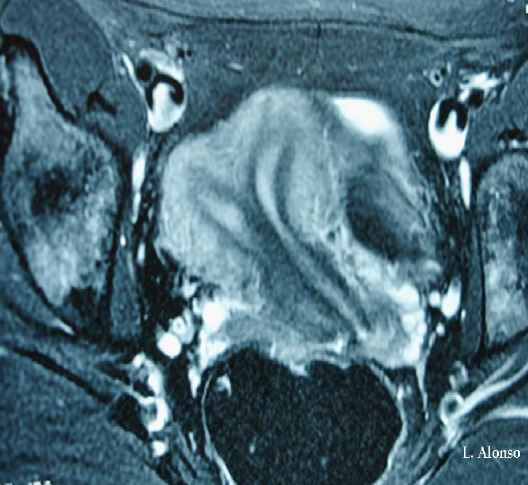

Son varias las técnicas de imagen utilizadas para el diagnóstico de las anomalías tanto uterinas como cervicales presentando distinto grado de exactitud diagnóstica. La ecografía 2D y la histerosalpingografía tienen un grado de diagnóstico menor a la resonancia magnética, a la que se le atribuye una exactitud para el diagnóstico de anomalías müllerianas entre un 96-100%, además la RMN permite el estudio del sistema urinario, que en determinadas ocasiones presenta malformaciones asociadas. El uso de la ecografía 3D ofrece cifras de exactitud diagnóstica similares a las de la RMN.